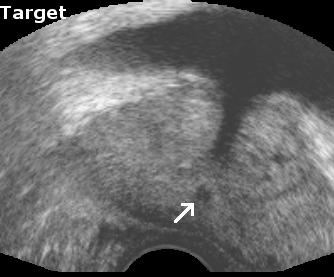

To measure reproducibility and registration success, 10 registrations were carried out for each volume pair from slightly perturbated start points by adding noise of 2mm and 2°. This yielded 10 transformations Tisubscript𝑇𝑖T_{i} that approximate the unknown rigid transformation between the prostate in both volumes. The average transformation T¯¯𝑇\overline{T} of the Tisubscript𝑇𝑖T_{i} was computed with the method presented in [9]. The euclidean distance error ϵEi=TiCT¯Csuperscriptsubscriptitalic-ϵ𝐸𝑖normsubscript𝑇𝑖𝐶¯𝑇𝐶\epsilon_{E}^{i}=||T_{i}\cdot C-\overline{T}\cdot C||, with C𝐶C being the image center, and the angular error ϵAisuperscriptsubscriptitalic-ϵ𝐴𝑖\epsilon_{A}^{i}, which corresponds to the rotation angle of Ti1T¯superscriptsubscript𝑇𝑖1¯𝑇T_{i}^{-1}\cdot\overline{T}, were used to compute the root mean square (r.m.s.) errors ϵEsubscriptitalic-ϵ𝐸\epsilon_{E} and ϵAsubscriptitalic-ϵ𝐴\epsilon_{A}. A registration was considered successful if ϵE<2.0subscriptitalic-ϵ𝐸2.0\epsilon_{E}<2.0mm and ϵA<5subscriptitalic-ϵ𝐴5\epsilon_{A}<5 degrees, and if the result T¯¯𝑇\overline{T} was visually satisfactory when superimposing both volumes in a composite image (See Fig. 2).

Reconstruction accuracy evaluation was more difficult to implement since there is no straight-forward gold standard. In some images, the needle trajectories from previous biopsies were still visible. In these cases, the trajectories were manually segmented, and the angular error between corresponding needle trajectories were used to evaluate rotational accuracy. Also, some patients had significant and clearly visible calcifications inside the prostate. The distances between segmented calcifications were used to determine the translational accuracy. Tab. 1 and Fig. 2 show the results of the evaluations.

Figure 2: Registration accuracy: (a) shows the target image, and (b) the aligned panorama image. In (c) both volumes are superimposed to illustrate registration accuracy for the urethra (arrow), and (d) illustrates the registration accuracy in the upper gland.